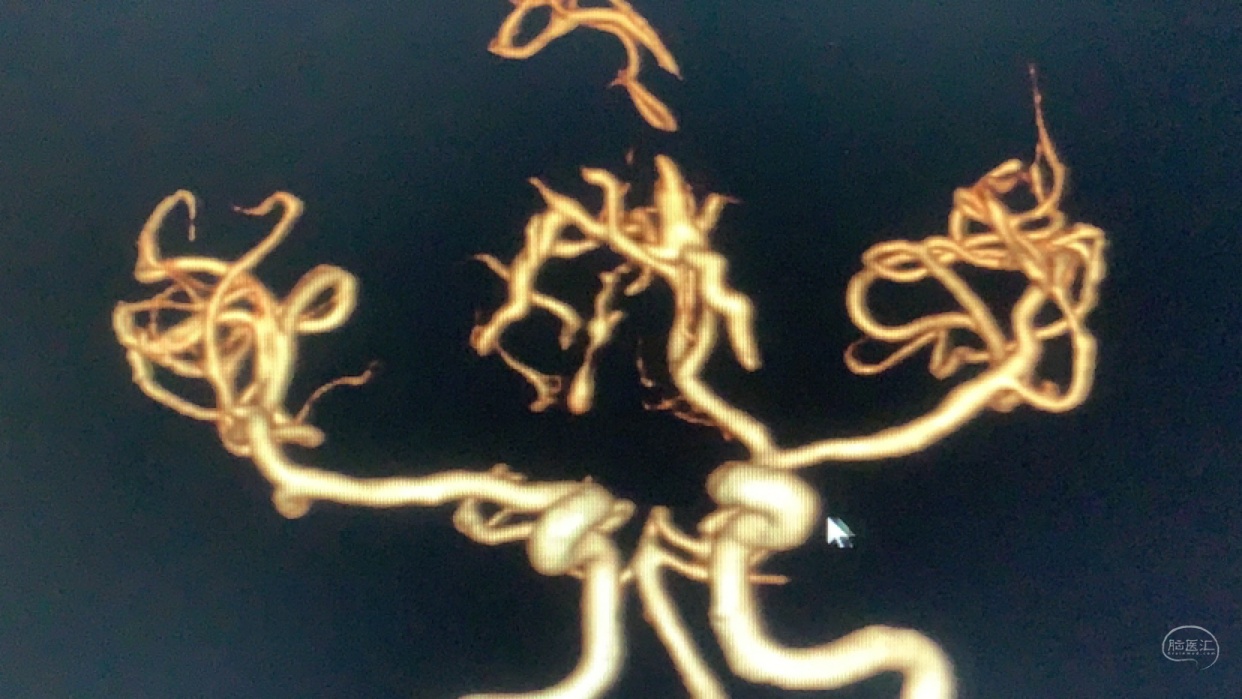

术前造影

神志昏迷双瞳散大对光反射迟钝入院,入院后甘露醇脱水加地米静滴后患者神经功能有改善,能摸索定位,瞳孔反射改善。考虑占位大直接切除可能出血多,拟术前栓塞处理,但造影发现栓塞不易风险高后放弃栓塞。